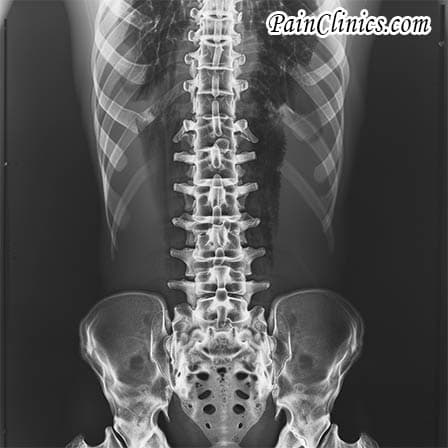

Advanced imaging tests, including MRI and CT scans, are crucial for examining the spine’s structure and identifying any post-surgical structural abnormalities. Moreover, radiological imaging methods such as X-rays and specialized bone scans are instrumental in evaluating spinal alignment and detecting fractures. These imaging techniques collectively provide a more detailed view of potential factors contributing to FBSS.